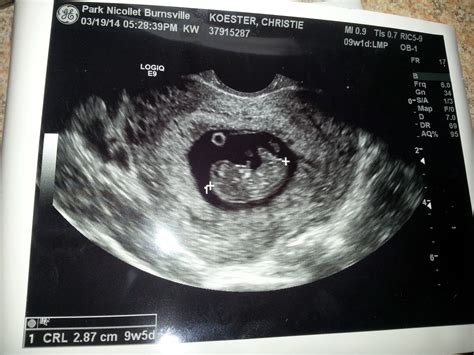

At 9 weeks, the fetus is still very small, but several key features can be observed during the 9 week sono:

• Heartbeat: One of the most exciting moments is hearing and seeing the fetus's heartbeat. At this stage, the heartbeat is usually visible and can be detected with a Doppler device.

• Gestational Sac: The gestational sac, which contains the fetus and amniotic fluid, is clearly visible.

• Yolk Sac: The yolk sac, which provides early nutrition to the embryo, is also visible.

• Embryo: The embryo itself is about the size of a grape and has a distinct shape. The head is large in proportion to the body, and the tail is still present.

• Neural Tube: The neural tube, which will develop into the brain, spinal cord, and nervous system, is forming.

• Limbs and Organs: The beginnings of the arms, legs, and internal organs are visible, although they are still in the early stages of development.